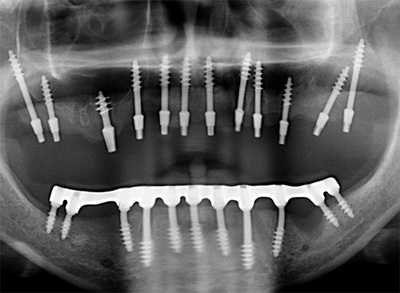

Вам сказали фигню! Вот снимок этой пациентки до лечения.

Но мы отвлеклись. Вот снимок пациентки после лечения.

Кроме зубов "мудрости" не удалено ничего. Тут проведено лечение корневых каналов, вкладки, коронки. Какие удаленные 22 зуба? Это бред СМИ, нацеленный на непонятную травлю. Конечно, кого заинтересует новость "пациентке не понравился результат лечения и она подала в суд", фу, уныло. А вот "шок!!врачи-убийцы рядом!! Схватили, выдрали 22 здоровых зуба!!и вкатали счет на миллион!!не допустим врачебного произвола!!!111" - вот это уже вызывает подрыв у очень многих.